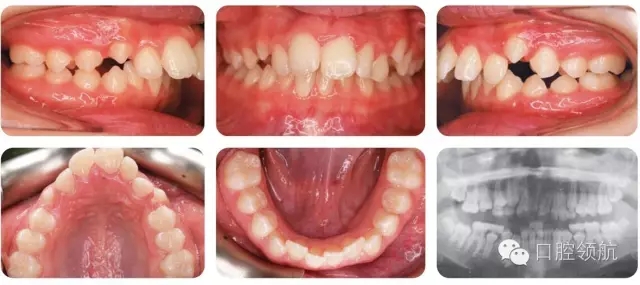

12歲的女性患者,由全科牙醫(yī)轉(zhuǎn)診。該患者健康情況良好,主訴是前牙前突(圖2.1)。

圖2.1

口內(nèi)相中的牙列處于哪一階段?

早期恒牙列。除LL7部分萌出以外,其余第二磨牙尚未萌出。

錯牙合的主要特點(diǎn)有哪些?

● 安氏II類1分類,深覆蓋,深覆牙合,下前牙咬在上前牙腭側(cè)黏膜。

● 右側(cè)磨牙1/2牙尖Ⅱ類關(guān)系,左側(cè)磨牙I類關(guān)系。

● 中線一致。

● UL2多生牙已萌出。

雙側(cè)磨牙關(guān)系為何不一致?

左上牙列存在一顆多生牙,但中線基本一致,說明UL6比正常位置偏遠(yuǎn)中,所以更接近I類關(guān)系而不是II類。